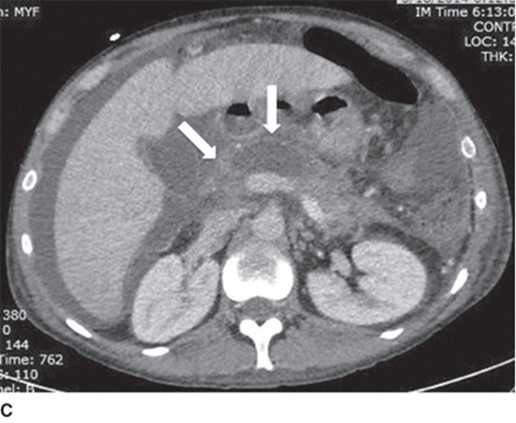

edematous pancreas bc acute pancreatitis

edematous panc with pseudocyst in tail of panc

normal panc with distinct borders